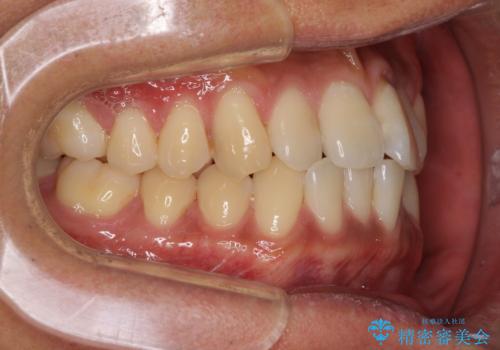

気になる前歯のデコボコをインビザラインで解消

- 前歯のデコボコを気にして来院された患者様です。

主に下顎歯列全体の後方移動とIPR(歯と歯の間を削る)によってデコボコが解消するように設計し、インビザラインにより治療を行うこととしました。

インビザライン矯正特有の、治療後半で前歯のみが強く接触する症状が発現し、咬み合わせ改善に期間を要することとなりました。